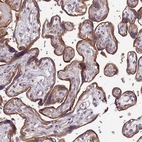

Immunohistochemical staining of human placenta shows strong cytoplasmic positivity in trophoblastic cells.